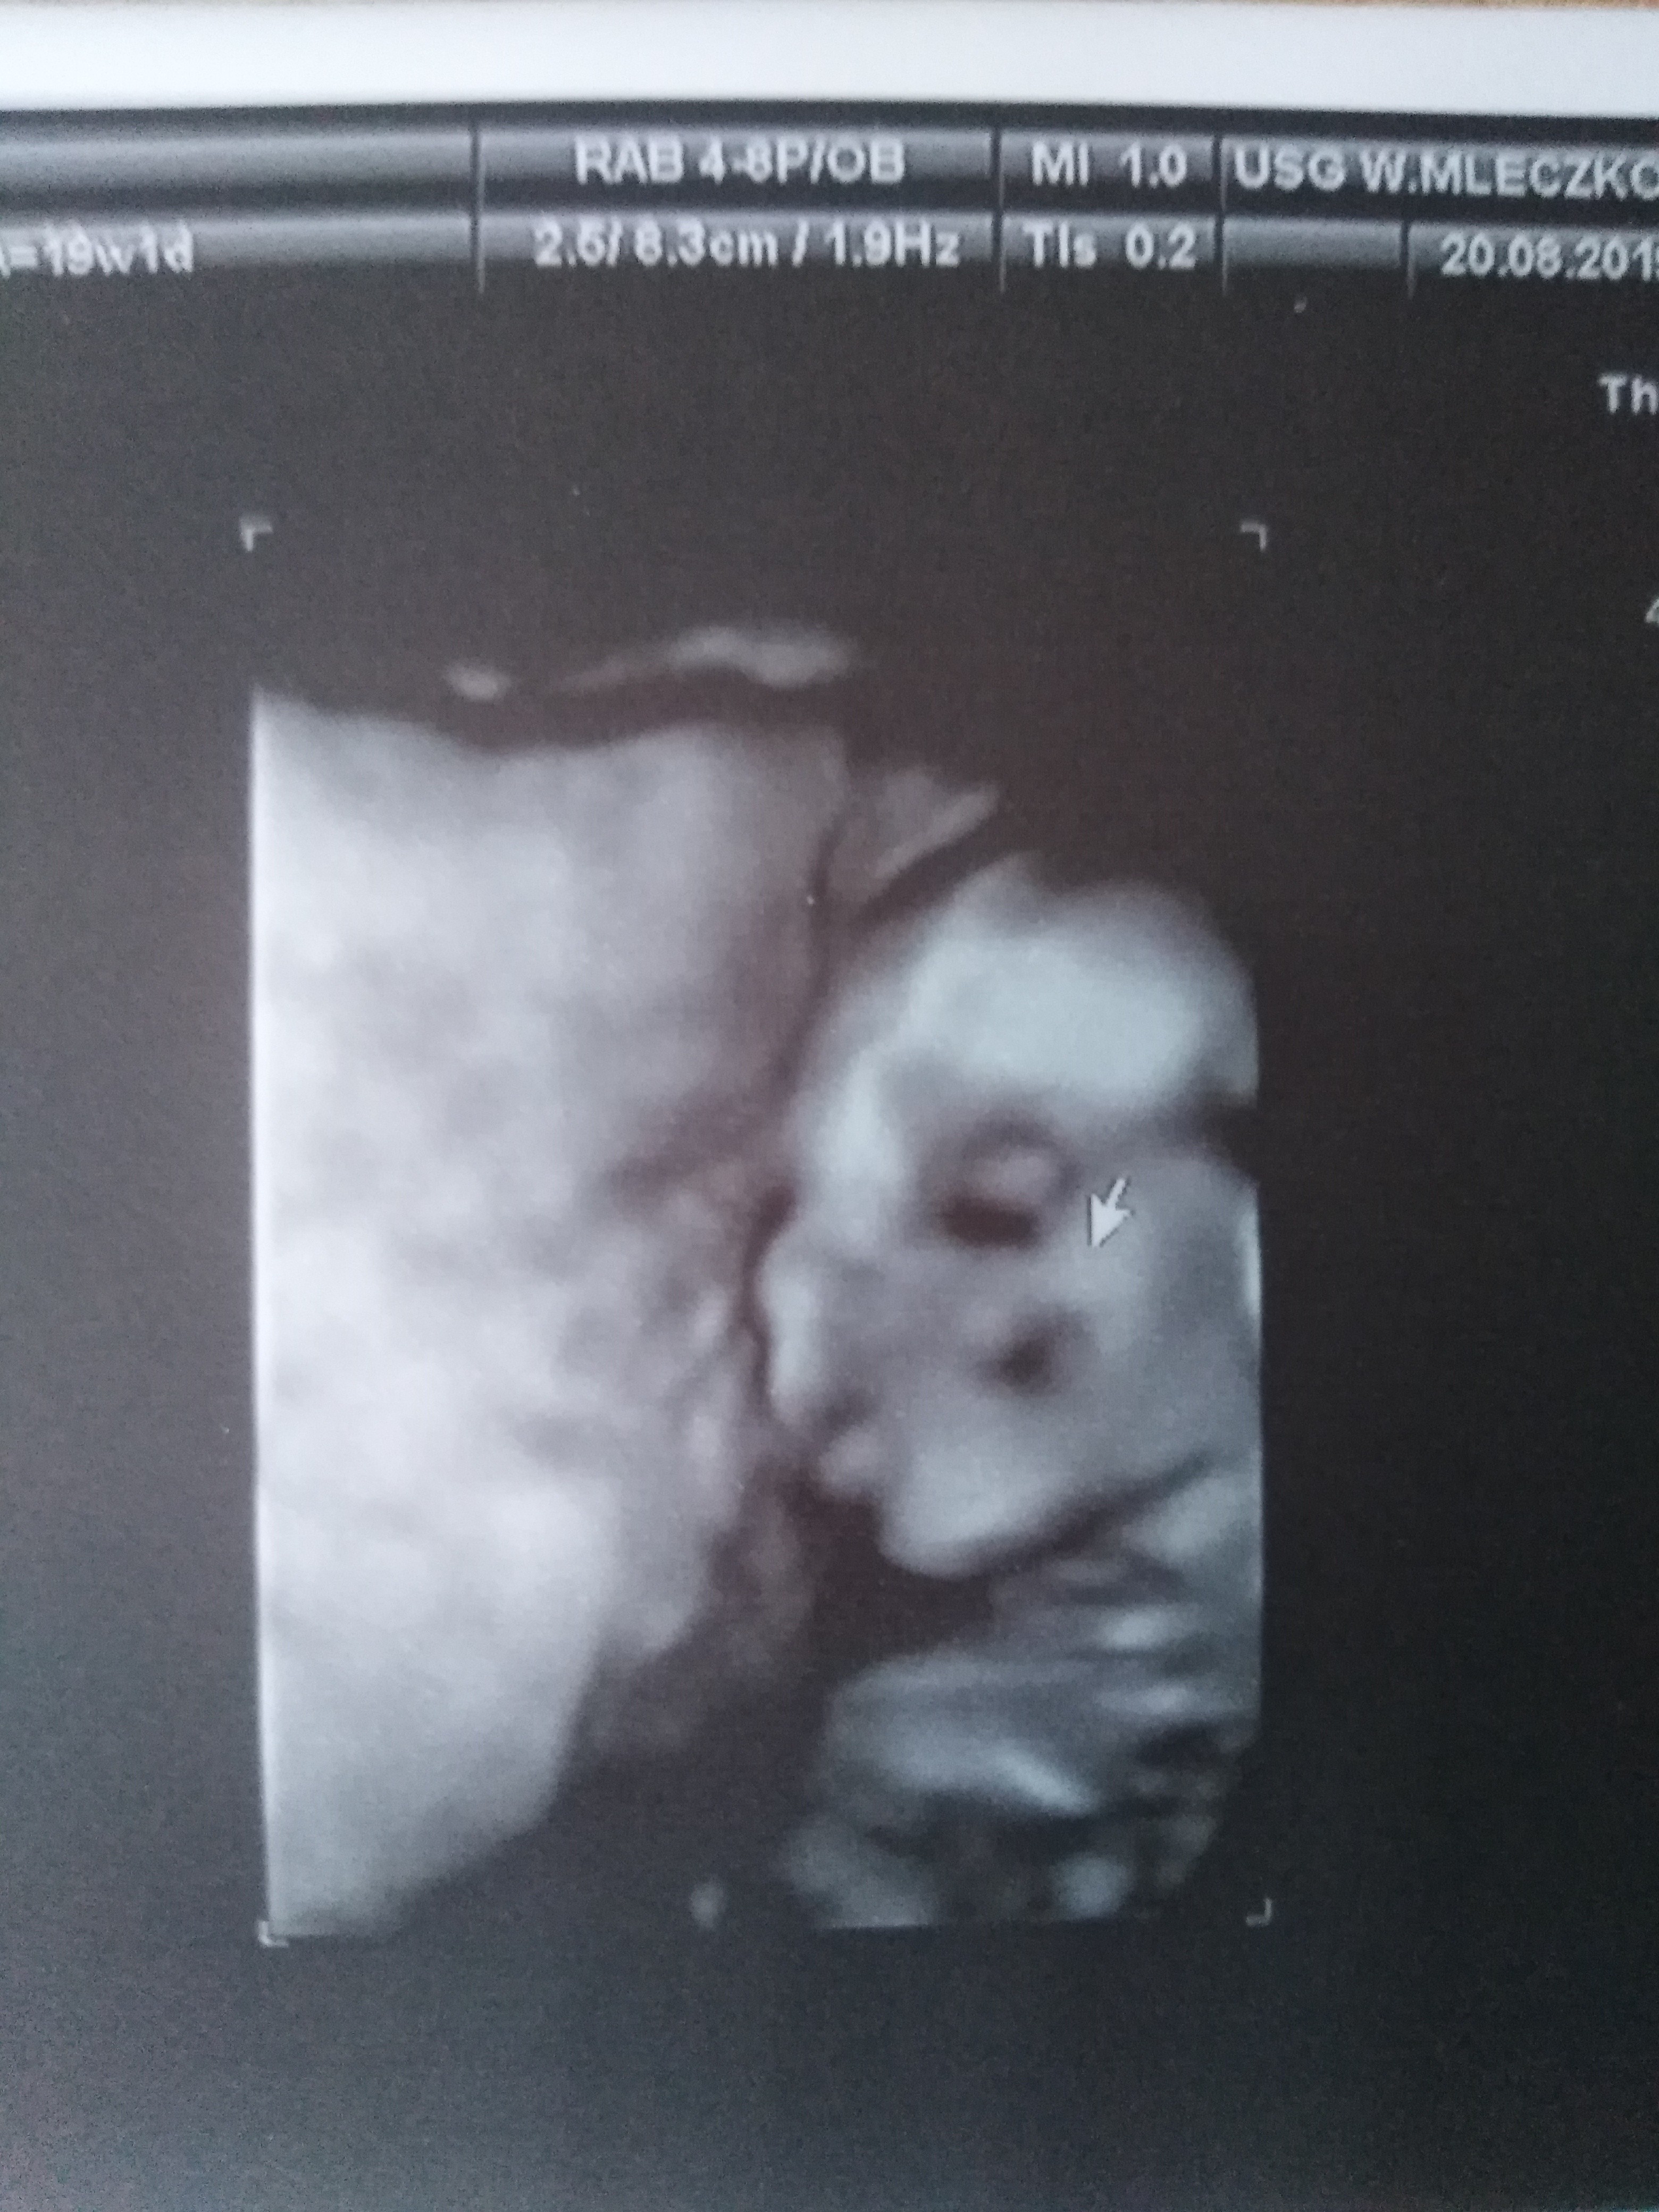

My z synusiem po wczorajszej wizycie :-) Po raz trzeci dostałam potwierdzenie że chłopczyk. Waży 316 g i ma się dobrze :-) Udało się dr złapać na zdjęciu twarzyczkę mój starszak (6 lat) stwierdził że wygląda jak zombiak ; -) Padam po dzisiejszej nocy nic prawie nie spałam. Jak na lewym boku się położyłam to jakaś dziwna kolka mnie chytała a na prawym boku budził mnie potworny ból pleców i prawej strony... :-/

Załączniki

• IMG_20190821_094912.jpg

IMG_20190821_094912.jpg

1,9 MB · Wyświetleń: 109